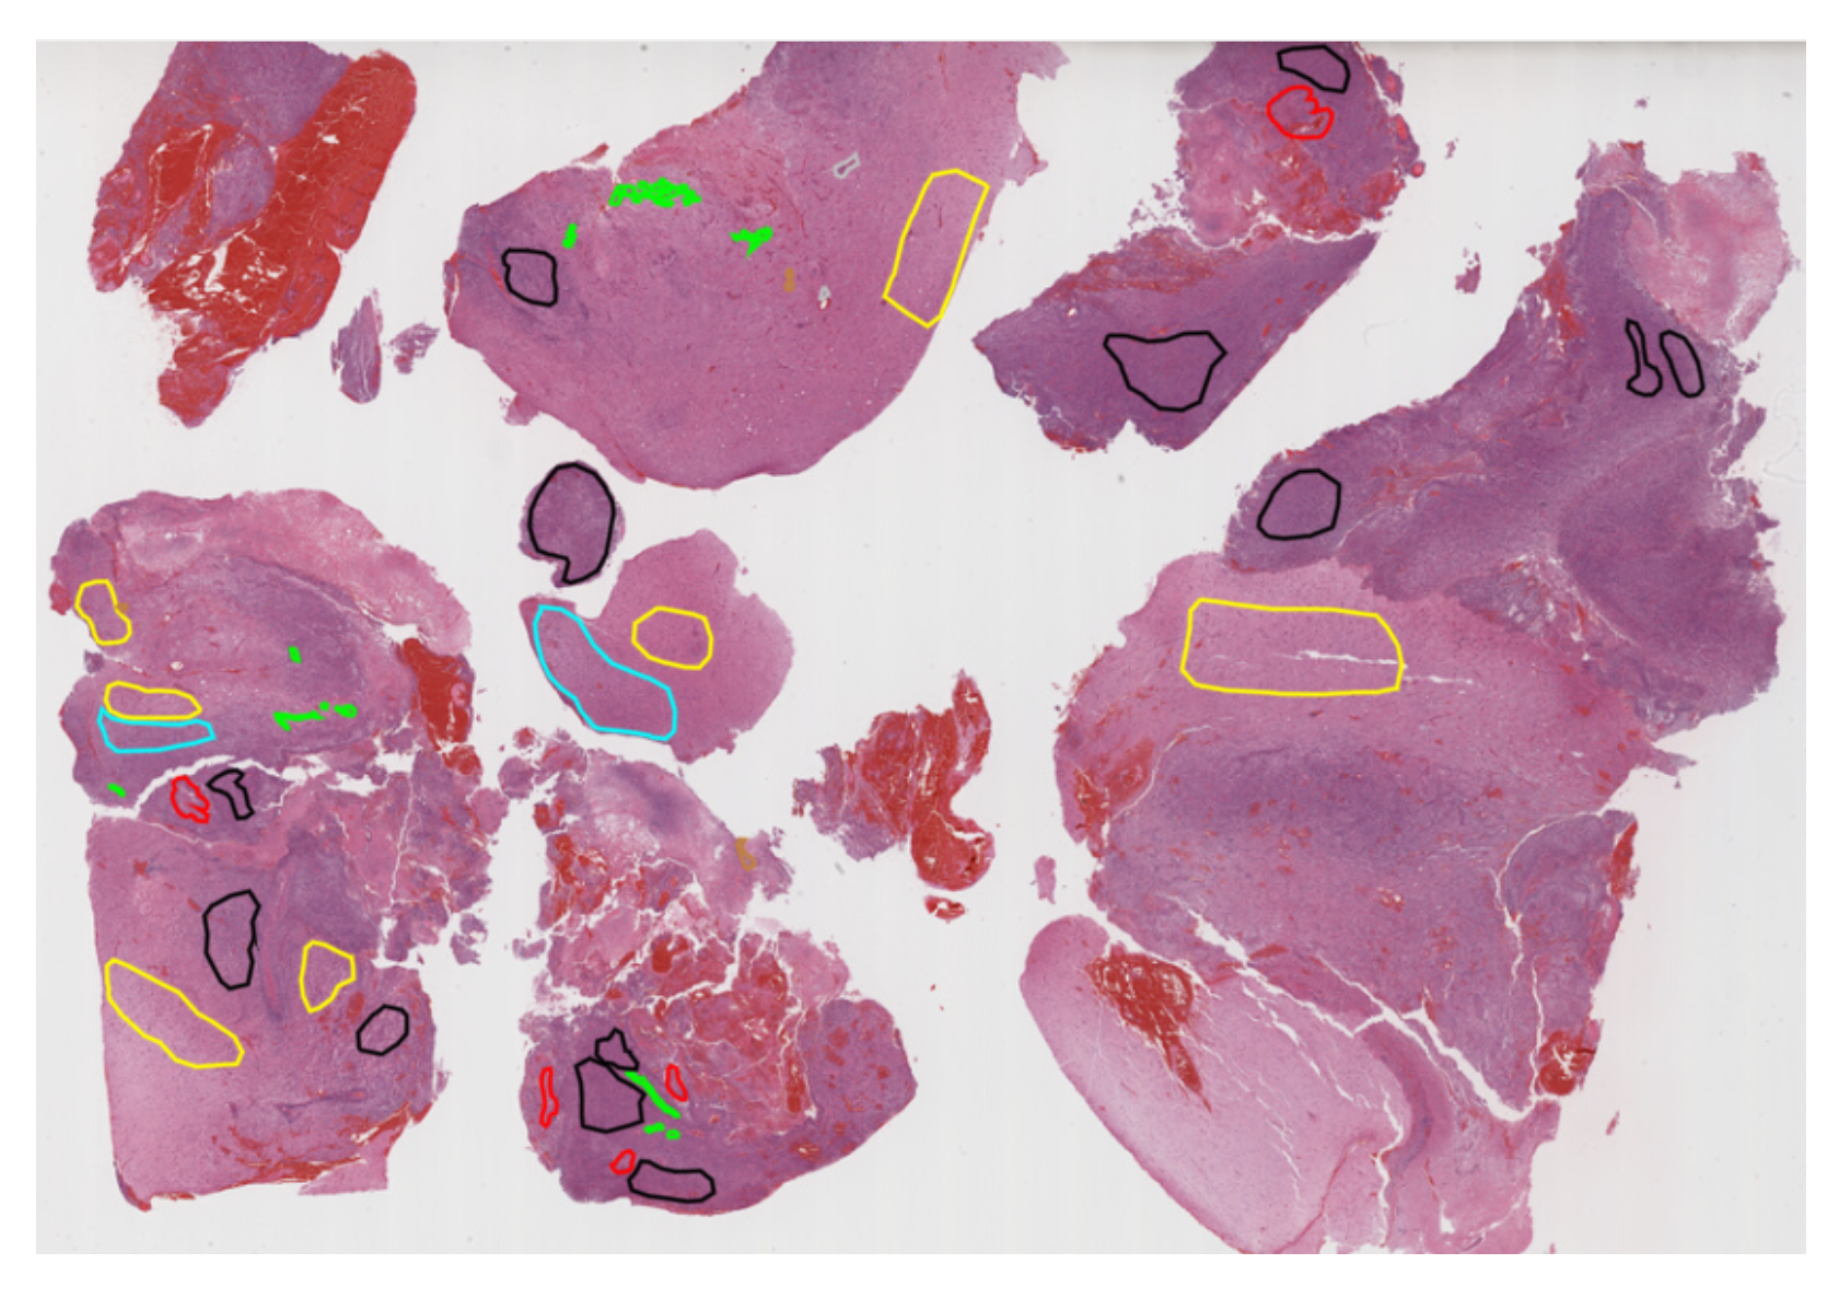

Pathology: Glioblastoma, the most common primary brain tumor in adults, has a poor prognosis, with median survival ranging from 12-18 months with treatment and only 4 months without. Its infiltrative nature and heterogeneous molecular and micro-environmental profiles make treatment challenging. Accurate diagnosis and assessment of tumor heterogeneity are critical for selecting effective therapies and potentially improving patient outcomes. The BraTS-Path Challenge leverages whole slide histopathology images (WSI) to enhance the understanding of glioblastoma by detecting various morpho-pathological features in digitized tissue sections. It draws on the gold-standard histopathology-based approach, which traditionally focuses on identifying features such as cellular tumor regions, necrosis, microvascular proliferation, cortical infiltration, and immune cell presence. By providing a robust dataset, the challenge aims to develop deep-learning models capable of automatically classifying these distinct tumor sub-regions with varied histological profiles. These models are designed to mimic and extend the gold-standard process, supporting more consistent diagnosis and grading, thus enhancing both research and clinical applications [32].The dataset included a retrospective, multi-institutional cohort of de novo diffuse gliomas. Expert neuropathologists annotated and segmented histological regions into patches for classification based on specific characteristics. The dataset consists of: 195,000 training data from 130 digitized tissue section; 25,000 validation data from 18 digitized tissue sections and 60,000 testing data from 40 digitized tissue sections. Nine histologic areas of interest are considered as classes.

Pathology: The preprocessing pipeline for H&E-stained FFPE tissue sections of glioblastoma multiforme (GBM) was specifically designed to facilitate detailed histological analysis:1) Patch Extraction and Standardization: Tissue sections annotated by expert neuropathologists are segmented into standardized 512 x 512 pixel patches. This size minimizes boundary noise and ensures comprehensive coverage of annotated regions.2) Quality Control: Only high-quality sections are included, excluding those with artifacts such as tissue folding, pen markings, or glass slippage.3) Patch Classification: Each patch is categorized based on its histologic features, which are used throughout training, validation, and testing to evaluate the challenges and accuracy of feature detection.This structured pipeline ensures high-quality data for histological studies, with each patch treated as an independent unit for comprehensive analysis [32].

Pathology: The annotation process adhered to a clinically-approved protocol, defined by expert neuropathologists, which provided detailed instructions on segmenting each histologic feature. For further details, refer to the challenge manuscript: [32]. Each case was assigned to an annotator-approver pair. To assess inter-rater variability, three cases were annotated by all annotators. Annotators varied in experience and rank, while approvers were highly experienced, board-certified neuropathologists with over 10 years of expertise.Once annotations were completed, they were reviewed by the approvers, who evaluated their quality alongside the corresponding tissue sections. If the initial annotations on a tissue section produced fewer than approximately 1,500 patches, that section was returned to the annotators for further refinement. This iterative process continued until the approvers approved the annotations. The segmented regions were then divided into patches and classified based on specific histologic features. This established a classification task focused on accurately identifying patches with distinct morphological characteristics.Histologic areas of interest for classification included:1) presence of cellular tumor (CT);2) pseudopalisading necrosis (PN);3) areas abundant in microvascular proliferation (MP);4) geographic necrosis (NC);5) infiltration into the cortex (IC);6) penetration into white matter (WM);7) leptomeningeal infiltration (LI);8) regions dense with macrophages (DM);9)presence of lymphocytes (PL);An example of the data and classes is illustrated in Figure x.